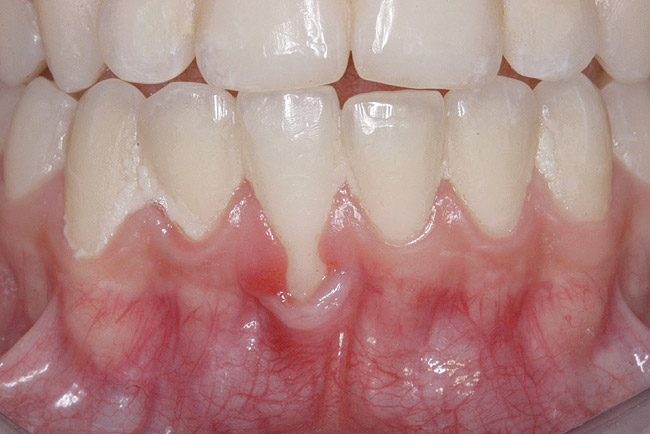

Fig 14. Post-orthodontic Miller Class II recession treated with a combined orthodontic-surgical approach. Clinical view 5 years after first orthodontic treatment showing GR of right lower incisor and a labially prominent root.

Figure 14

Fig 15 Same patient 2 years later showing worsening of GR and inflammation.

Figure 15